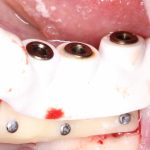

Далее, можем приступить к установке имплантатов. Разумеется. по хирургическому шаблону:

Последняя картинка даёт представление о том, какой объем костной ткани мы «нарастили».